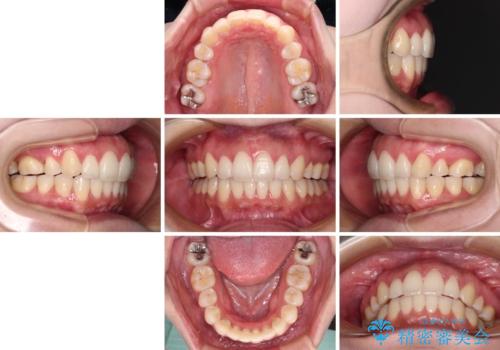

- 抜歯矯正の後戻りで前歯が突出してきていることを気にして来院された患者様です。

口元の突出感を改善するにあたり、抜歯矯正は行うことができないため、奥歯の後方移動とIPR(歯と歯の間を削る)により達成することとしました。

再度後戻りしたときに対応しやすいよう、インビザラインにて矯正治療を行うこととしました。

しっかりと装着時間を守り、ゴムかけにも協力していただいたので、口元を引っ込めることができました。